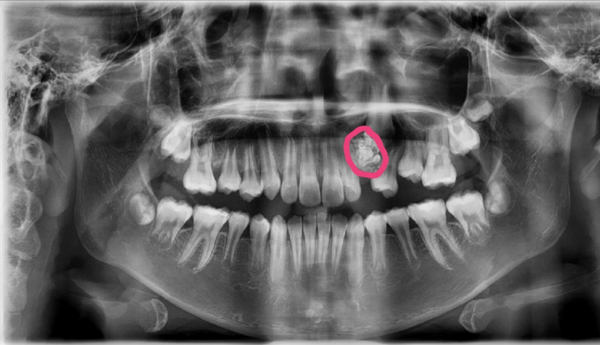

Tuy nhiên, kết quả chụp răng toàn cảnh của bệnh nhân cho thấy có khối u răng ở gần vị trí khuyết. Bác sĩ chỉ định phẫu thuật loại bỏ khối u.

Hình ảnh khối u trên phim chụp X-quang

Khối u răng được loại bỏ với gần 20 chiếc răng nhỏ li ti có đầy đủ thân, tủy, chân răng. Sau khi loại bỏ khối u, các bác sĩ đặt khí cụ để kéo răng nanh ngầm về đúng vị trí.